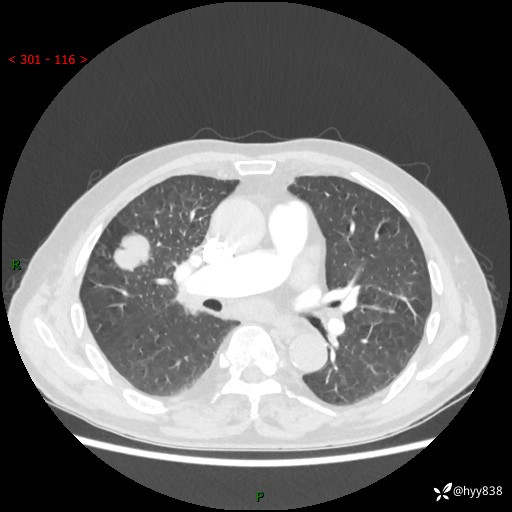

69岁/男,间断咳嗽伴气促、下肢水肿。临床拟诊肺栓,偶发肺均质强化结节--结果公布

【患者信息】:69岁/男

【主诉】:间断咳嗽伴气促、下肢水肿2周

【现病史及既往史】:患者2周来无明显诱因出现咳嗽,咳少量白痰,不易咳出,伴有气促,呈间断发作,症状与活动费力相关,以夜间为甚,不能平躺入睡,偶有憋醒,无胸闷胸痛、无发热、无头晕、头痛等不适,伴有双下肢中度水肿,就诊于当地县人民医院门诊,完善相关检查提示:左下肢深静脉血栓形成,未予以特殊处理,今患者为求进一步诊治来我院就诊,拟“心衰”收入我科。 起病以来,患者精神、饮食、睡眠可,大小便如常,体力明显下降,体重未见明显减轻。

【检查】:胸部CT增强